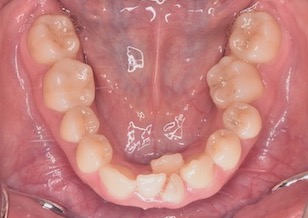

矯正前

Before Ⅱ

上下顎歯列に重度の叢生(ガタガの歯並び)を認めます。下顎の右側側切歯は先天欠如を認めました。上顎右側側切歯は舌側に転位し反対咬合になっています。

また左側の上下顎第1大臼歯がすれ違い(交叉咬合)となっています。~すれ違い咬合の改善は難易度が高い治療となります。~